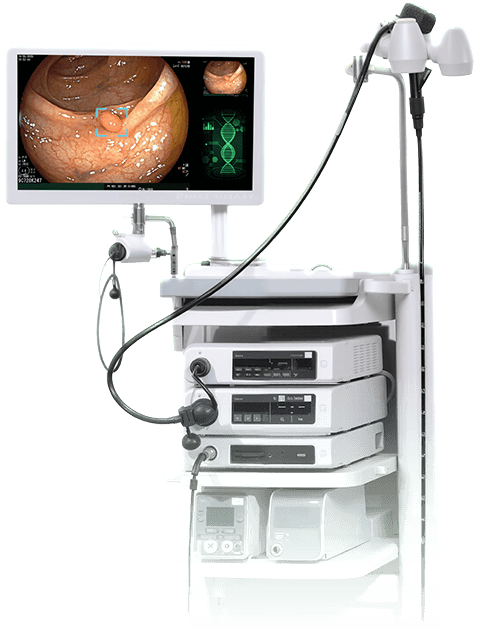

Mục tiêu tầm soát bệnh chính xác để trị hết bệnh, đem lại hạnh phúc cho người bệnh, Phòng khám đầu tư hệ thống máy móc tân tiến hiện nay, giúp bác sĩ đánh giá chính xác tổn thương và giúp sinh thiết chính xác vị trí tổn thương.

TRANG BỊ THIẾT BỊ HIỆN ĐẠI BẬC NHẤT

Với hệ thống máy nội soi hiện đại cùng công nghệ chẩn đoán hình ảnh tiên tiến, chúng tôi tập trung phát triển dịch vụ nội soi chuyên sâu nhằm phát hiện sớm và chính xác các bệnh lý tiêu hóa.